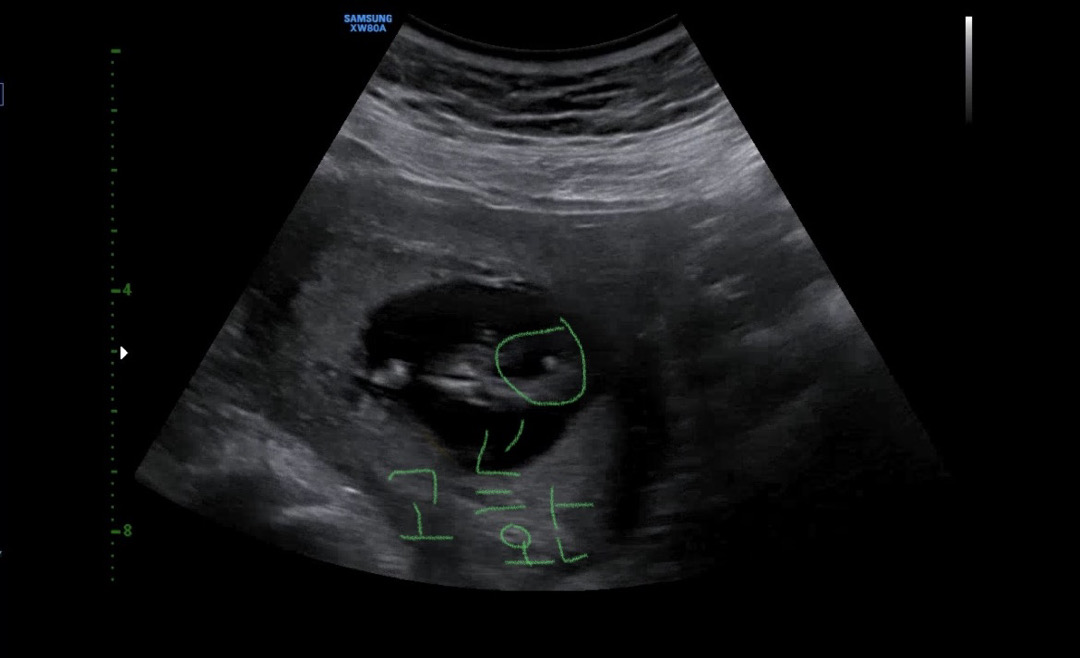

둘째도 아들?

13주1일차 오늘 니프티하고 1차 기형아 검사도햇는데 선생님이 힌트를 조금 주었는데 정확하진 않은데 남자아이같다고… 생식기가 조금씩 들어갈 시기에 안들어가져잇는거 같다고ㅋㅋ 첫째도 아들인데 ㅋㅋㅋㅋㅋ 반전은 없겟지? 반전잇으신분 계실까요 ? 나는 아들 복 이 많은갑다 생각해야지 ㅋㅋㅋㅋ